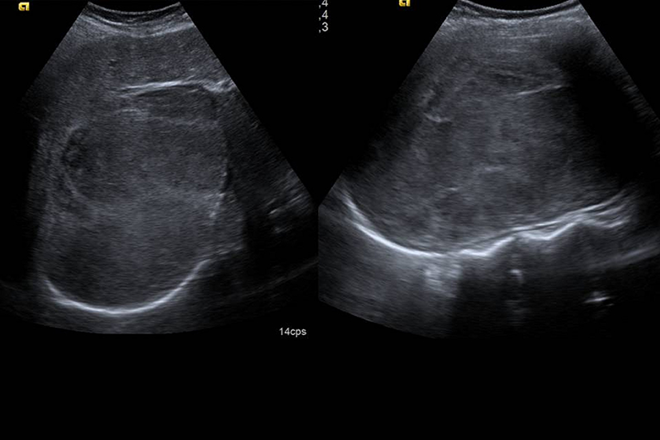

Ecografía hepática: lesiones focales y enfermedades difusas

La ecografía hepática es actualmente la primera técnica diagnóstica para la detección y caracterización de la mayoría de las lesiones del hígado, especialmente en la detección de lesiones focales o en el seguimiento de las enfermedades hepáticas crónicas. No solo se utiliza el modo B, sino también el doppler color